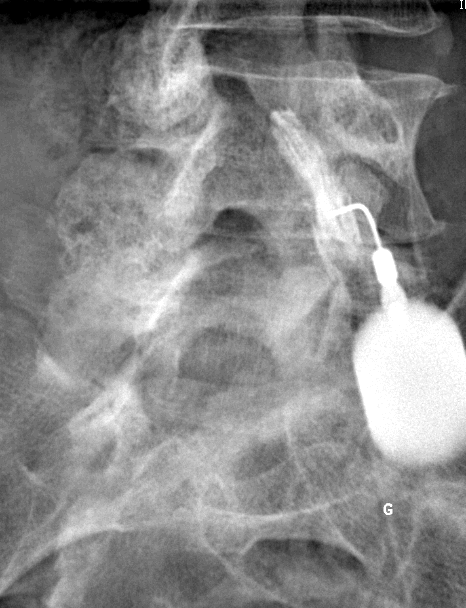

Infiltration de l'articulation coxo-fémorale (hanche).

Infiltration du rachis au niveaux des interlignes articulaires postérieurs (images 1, 2, 3, 4 et 5)